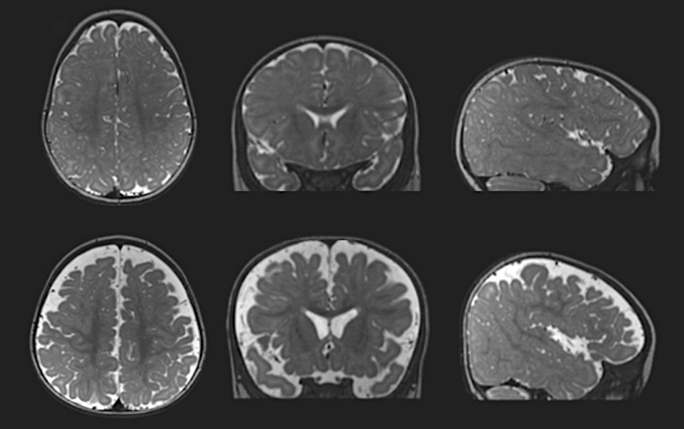

Un algorithme combinant différentes mesures (dont le sexe, l'âge, l'excès de LCR et le volume cérébral à l'âge de 6 mois) a permis de prédire avec une précision d'environ 70 % quels bébés de la fratrie ont été diagnostiqués autistes par la suite, comme l'ont montré les travaux de M. Shen. Cependant, l'excès de liquide cérébral ne permet pas de prédire l'autisme avec une certitude absolue, explique Jared Nielsen, professeur adjoint de neurosciences cognitives et comportementales à l'université Brigham Young de Provo, dans l'Utah.

En soi, le volume du LCR n'est peut-être pas suffisant pour faire des prédictions avec un niveau de certitude cliniquement significatif ; les chercheurs devraient le combiner avec d'autres mesures cérébrales ou traits comportementaux, explique Nielsen. "Nous avons besoin d'algorithmes peut-être plus compliqués qui combinent de nombreuses sources d'information et pas seulement la quantité de liquide qui entoure le cortex cérébral."